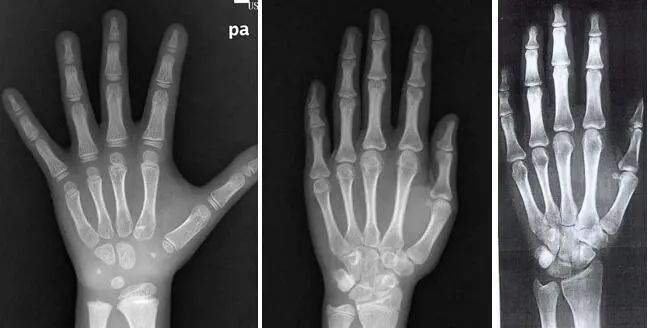

3个年龄相同的孩子,身高不同,骨龄也不同!

简单来说,骨龄就是骨骼的年龄,需要借助骨骼在X光摄像中的特定图像来确定。

只要孩子能配合伸出自己的左手(左手未成功时,右手可替代),将左手伸直张开放在指定位置5秒钟,即可完成骨龄片。

灯亮以后,小手不要动,左手的照片就有了!

拿出你家宝贝左手的正位X光片,图中圈出的位置是中节指骨3,当它的骨骺和骨干一侧或两侧等宽时,就意味着进入了猛涨期,要猛“蹿个儿”了!注意!!!当进入青春期后,骨龄亮起红灯,长高进入尾声,身高能干预的空间已经很有限了!

看看你家宝贝的骨龄X光片长什么样?

一般来说,男孩骨龄10.9岁、女孩骨龄8.8岁,进入猛长期。